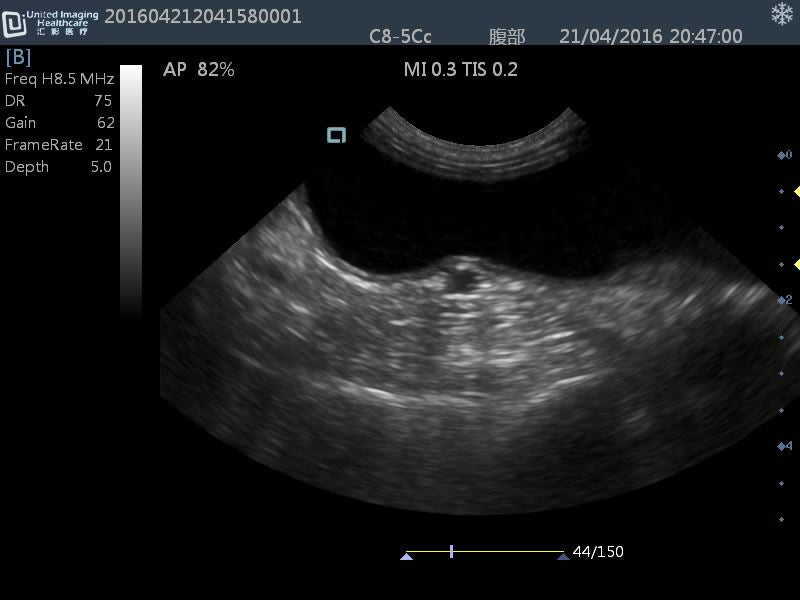

Micro-convex(R15): C8-5Cc

- Application: General small abdomen and cardiac

- Equine musculoskeletal and abdomens

- Number of element: 80

- Center frequency: 6.5MHz

- Working frequencies: 5 – 9MHz